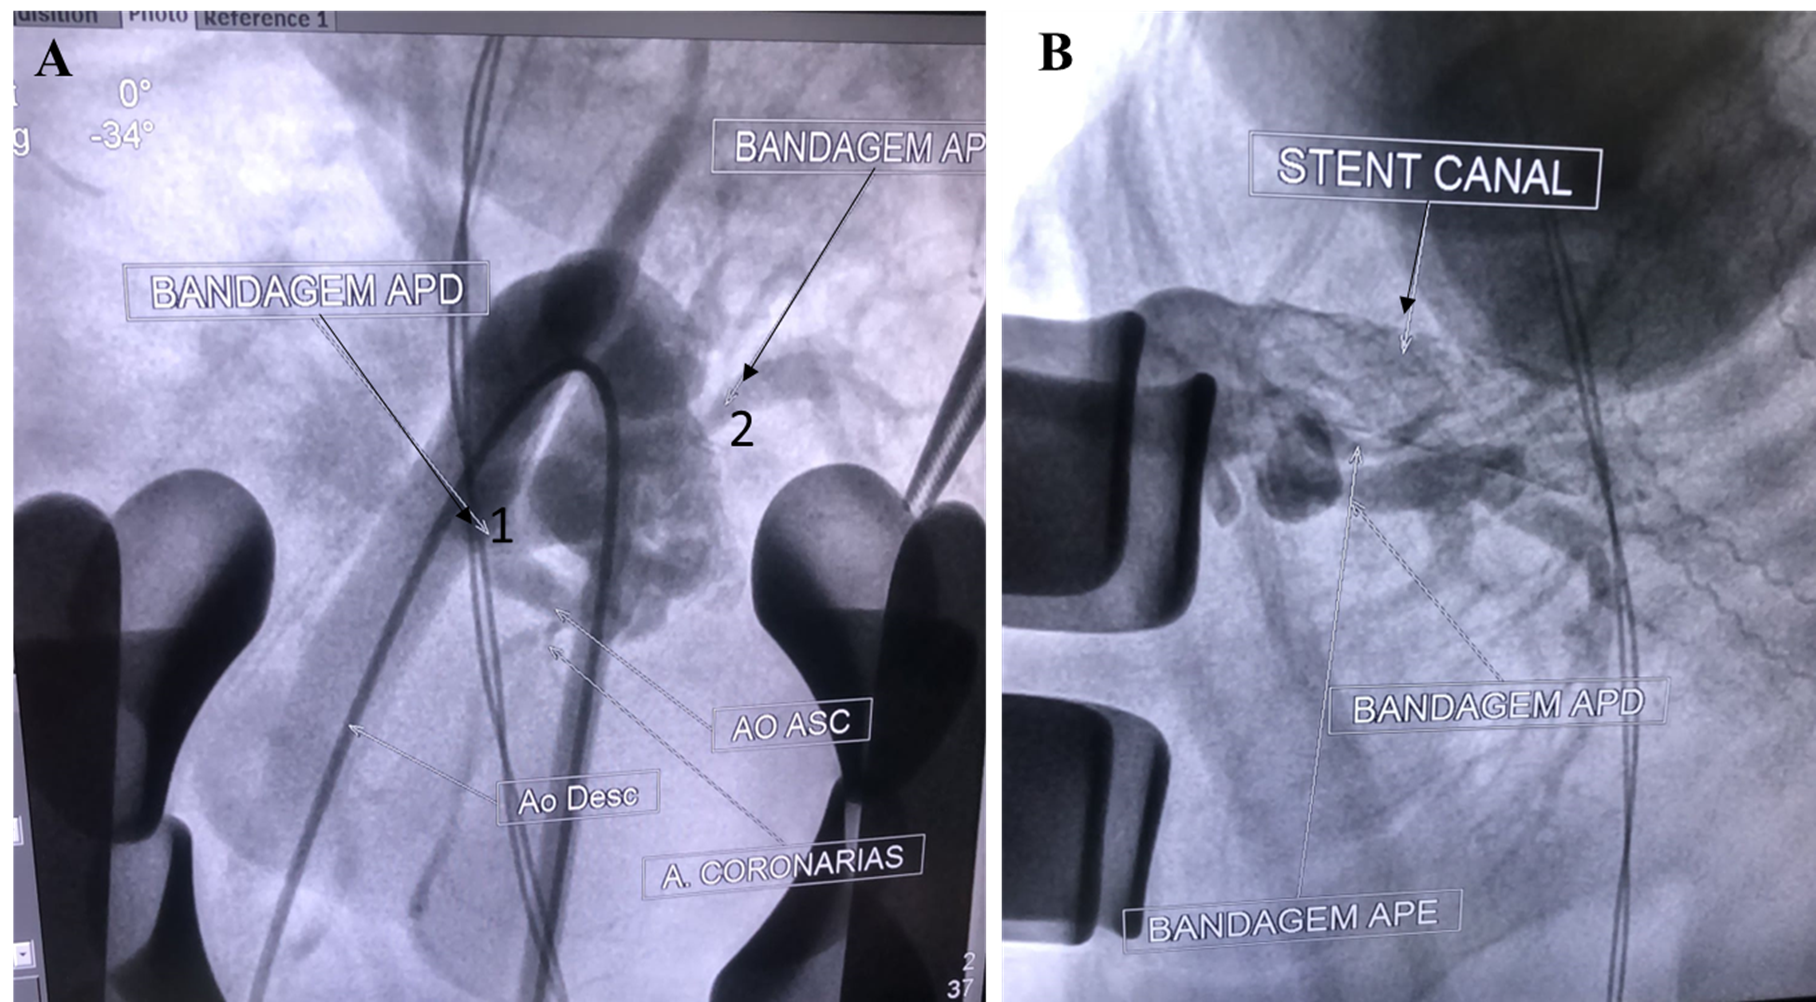

Stenting the Ductus Arteriosus of a Patient with Tetralogy of Fallot and Trisomy 18: Case Report and Updated Review

Márcio Erlei Vieira de Sá Filho, Marina Ayres Delgado, Bruno Vinicius Castello Branco, David Ribeiro do Nascimento

bjcr97